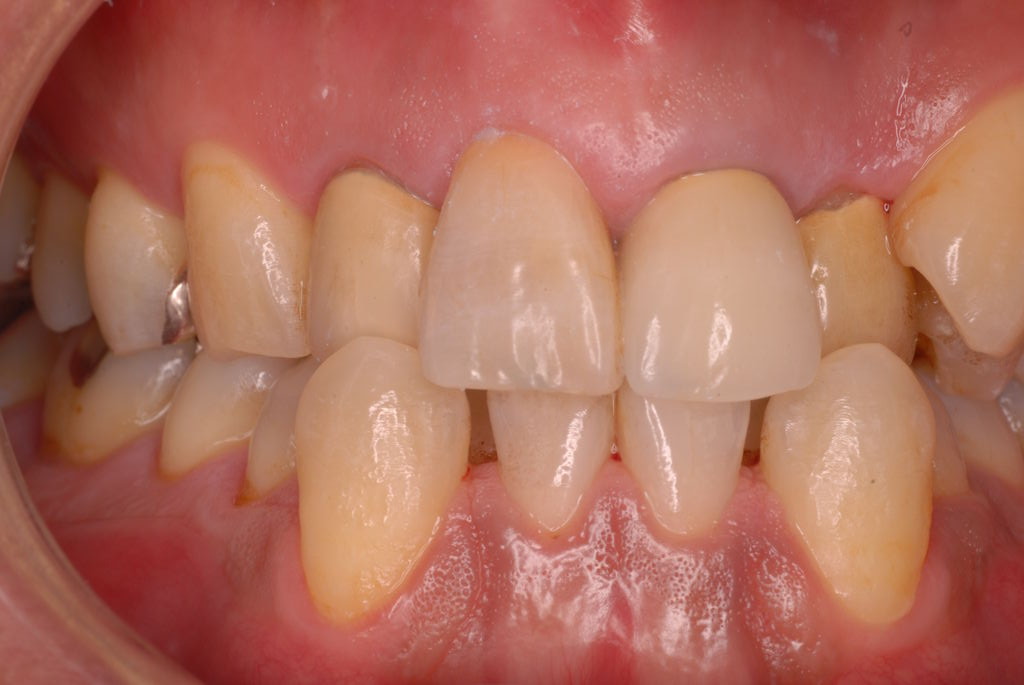

親知らずを取ることを嫌がる方が多いのですが、もし親知らずとその隣の14歳大臼歯の間に虫歯ができたり歯周病を罹患した場合、どれほど治療が大変で再発も起こりやすいか理解できない方がおおいのです。